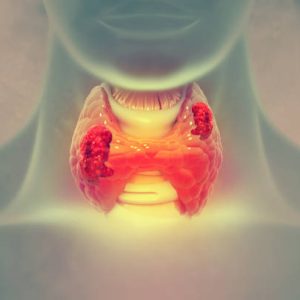

Thyroid & Hormonal Disorders

>>Natural therapies to balance hormones and improve thyroid function.